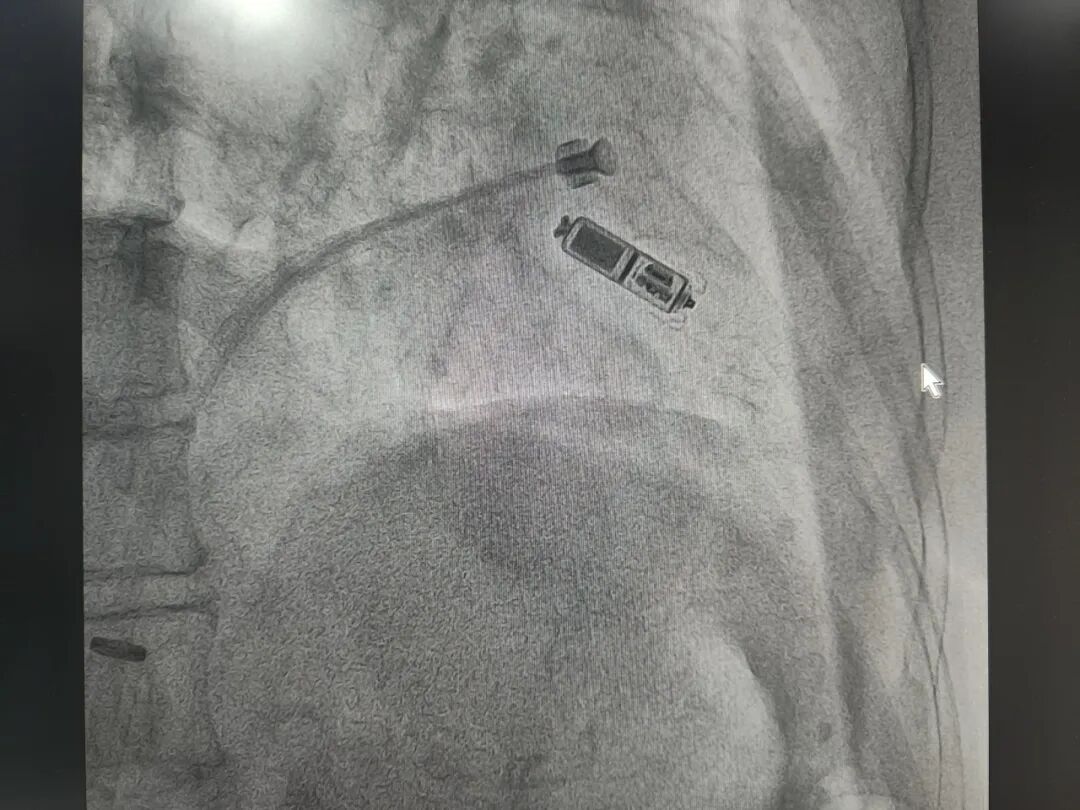

近日,一位90岁高龄的患者在我院成功完成了兴宁市首例无导线起搏器Micra VR(又称“胶囊起搏器”)植入术。术后患者恢复迅速,困扰许久的头晕、心悸症状显著缓解。这标志着我院在心律失常的微创介入治疗领域迈入了崭新的“无导线时代”。 “慢下来”的心脏,让生活提心吊胆 林阿婆年逾九旬,患有高血压、冠心病、糖尿病等多种基础病,身体条件较差。近期,她频繁感到头晕、心悸不适,检查发现心率最慢时仅有30次/分钟,心脏这台“发动机”时常“怠速”,导致全身供血不足,随时有晕厥甚至心跳骤停的风险。 高龄多病,传统手术面临挑战 对于此类心动过缓,植入心脏起搏器是最有效的治疗方法。然而,面对这样一位高龄且合并多种慢性疾病的患者,传统的起搏器植入术需要制作皮下囊袋并植入电极导线,手术创伤相对较大,术后存在囊袋感染、血肿、导线移位或断裂等风险,患者及家属对手术安全性与康复过程充满担忧。 微创“胶囊”技术,点燃希望之光 经过心血管内科团队严谨评估,并与患者家属充分沟通后,决定为其施行最先进的Micra无导线起搏器植入术。本次手术特邀广东省人民医院心血管内科刘洋教授莅临指导,与我院心内科团队共同完成。 无导线起搏器仅如一颗维生素胶囊般大小,重量约2克。它彻底摒弃了传统起搏器的“脉冲发生器(盒子)”和“导线”,通过患者腿部的股静脉穿刺,将起搏器直接递送至心脏内部并牢固附着在心壁上。这一技术具有创伤极小、无皮肤切口、无囊袋、恢复快、并发症风险显著降低等突出优点,尤其适合高龄、消瘦、合并多种疾病或存在传统手术高风险因素的患者。 专家引领,精准操作,半小时重启“心”生 手术当日,在刘洋教授的带领下,心内二科蓝雄师主任、刘文医生等心内科团队的密切配合,手术仅在局部麻醉下进行。通过微创穿刺,将胶囊起搏器经血管精准输送至心脏右心室理想位置,测试参数优良,起搏功能良好。整个手术过程仅耗时约30分钟,患者术中清醒,仅感觉腹股沟区轻微胀感。 快速康复,彰显技术优势 术后患者恢复平稳,心悸、头晕症状很快消失。在医护团队的精心照料下,患者已于术后早期下床活动,生活质量得到即时改善。此次手术的成功,不仅为这位超高龄患者解除了疾苦,也充分展现了无导线起搏器技术的巨大优势。 此次无导线起搏器植入术的成功开展,是我院心血管内科在心律失常介入治疗领域的一项重要突破。它体现了我院紧跟医学前沿技术,不断提升疑难危重症诊疗能力的决心,也彰显了医院坚持以患者为中心,采用更安全、更微创、更高效的技术方案,为每一位患者提供个性化、高质量医疗服务的宗旨。未来,我院将继续探索和应用更多先进技术,为广大市民的心脏健康保驾护航。 供稿:刘子斌 刘 文 编辑:刘子斌 责编:周文锋 审核:何 凯 |